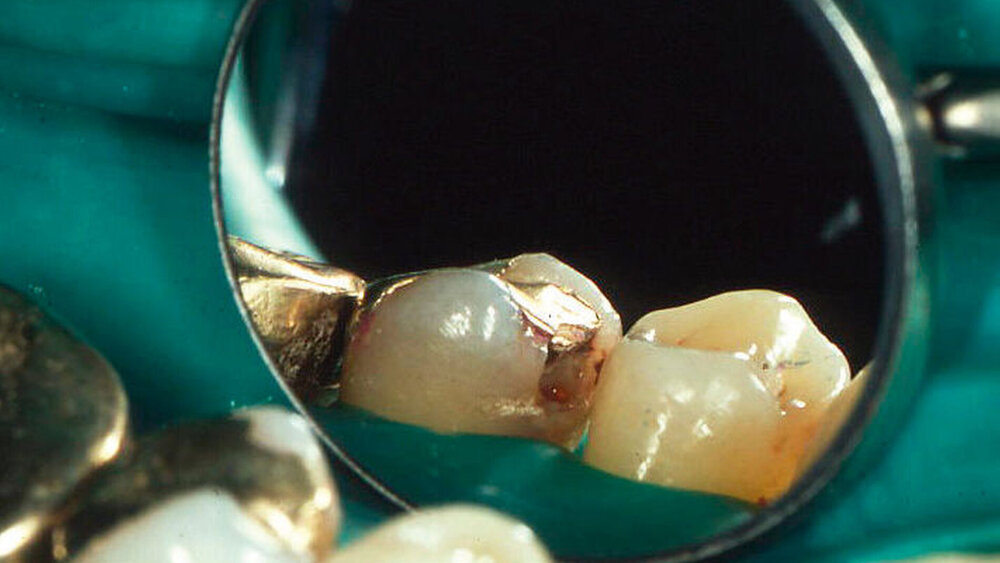

In Abbildung 1 werden etwa 30 Jahre alte Amalgamrestaurationen einer 60-jährigen Patientin gezeigt. Die Patientin wünschte eine Beratung mit der Frage: „Plomben erneuerungsbedürftig?“. Eine klinische und röntgenografische Untersuchung ergab keine Hinweise auf klinisch relevante Schäden, die ein sofortiges Eingreifen erforderlich gemacht hätten. Die Patientin wurde darüber aufgeklärt, dass bei ihr ein erhöhtes Risiko für Frakturen an den Restaurationen oder an den Zahnhartsubstanzen bestehe, die man allerdings im Eintrittsfall restaurativ angehen könne. Sie favorisierte zunächst ein Monitoring (Belassen und Beobachten). Acht Jahre später wurde wegen einer Randleistenfraktur eines Molaren eine Reparaturrestauration eingebracht (Abbildung 2). Sechzehn Jahre später wurden zwei weitere kleine Korrekturen vorgenommen (Abbildung 3). Nach 20 Jahren (Abbildung 4) war die nunmehr 80-jährige Patientin mit ihren inzwischen circa 50 Jahre alten Amalgamfüllungen immer noch sehr zufrieden. Vor diesem Hintergrund erscheint es angebracht, Restaurationen nicht voreilig als „insuffizient“ zu betrachten.

Abbildungen 1–4: Nachbeobachtungen und Reparaturen bei 30 Jahre alten Amalgamrestaurationen über einen Zeitraum von weiteren 20 Jahren

Ausgangssituation